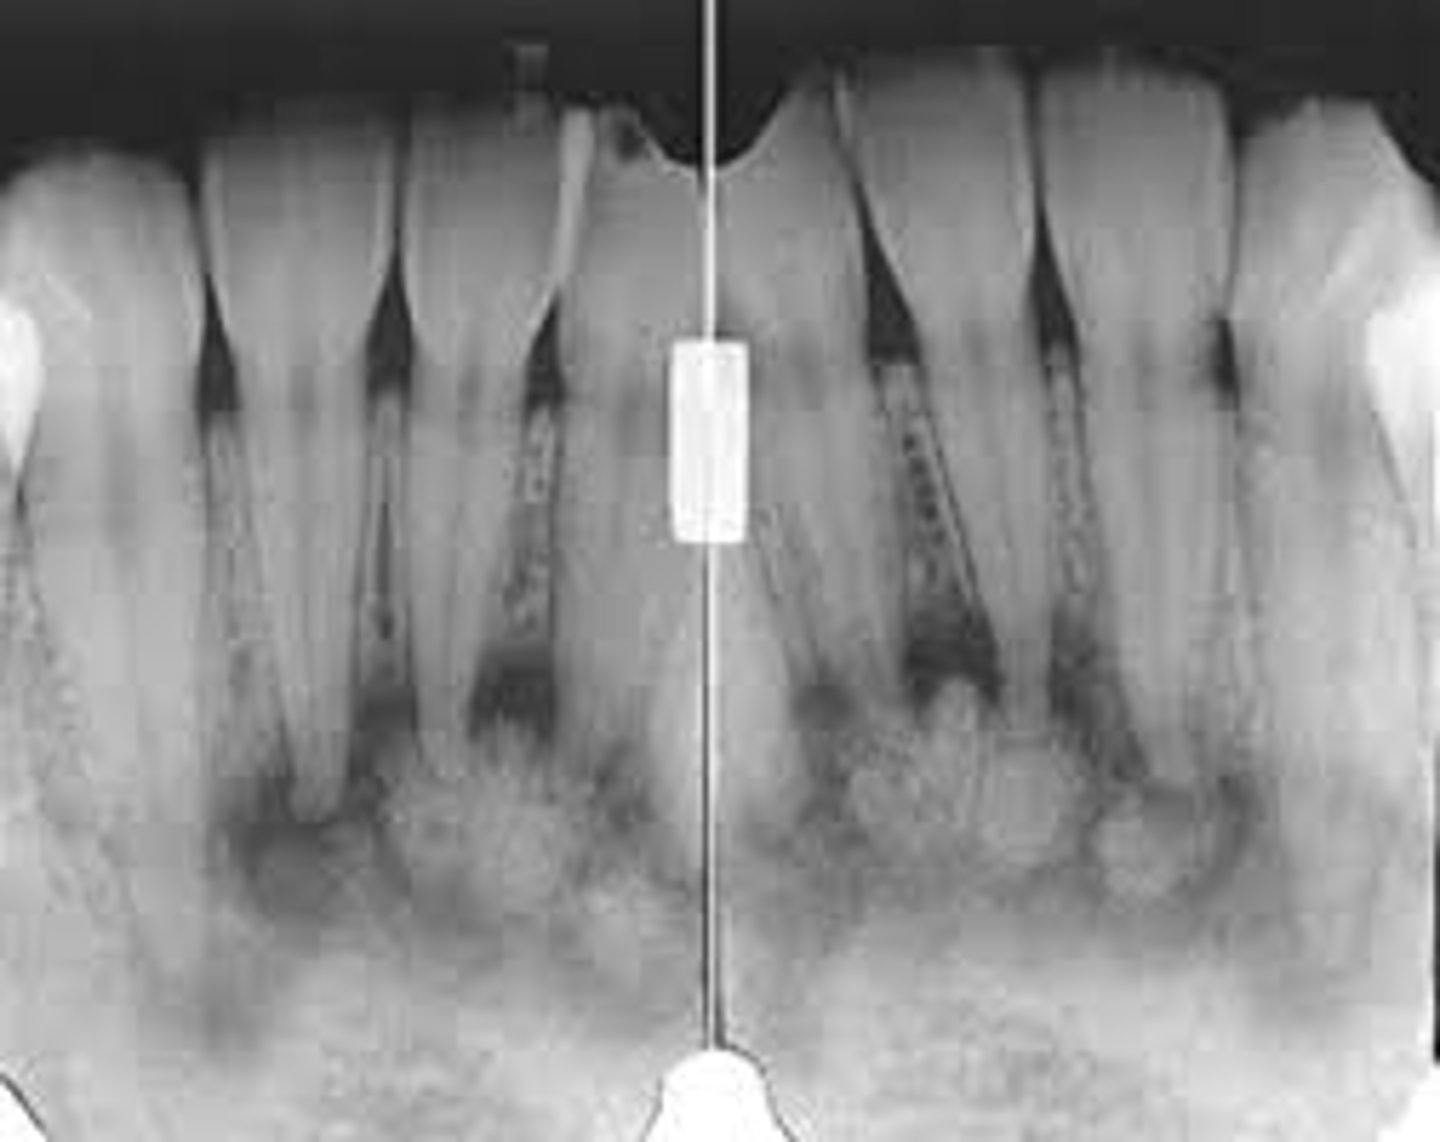

what is this?

what is this radiolucent area in the image?